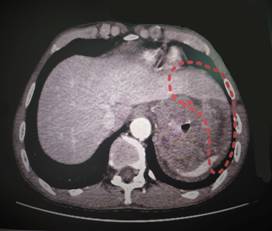

一年前,急诊来了位腹痛患者(阿辉),我科接诊后根据患者腹部增强CT,考虑存在腹腔肿瘤、肝占位性病变,进而引起上消化道不完全性梗阻。收住入院后积极治疗缓解梗阻的同时,我们给患者做了进一步检查,而检查的结果如晴天霹雳般让患者及家属陷入绝望。增强CT影像显示,患者左上腹胃底巨大占位,周边累及肝脏、隔肌(图1)、脾脏(图2),并破入胸腔,当时考虑:胃恶性肿瘤伴周边侵犯,已失去手术机会,预后极差。得知病情的阿辉,陷入痛苦的思想斗争,一度想要放弃治疗,拒绝输液、拒绝检查。

图1 肿瘤侵犯肝脏、膈肌